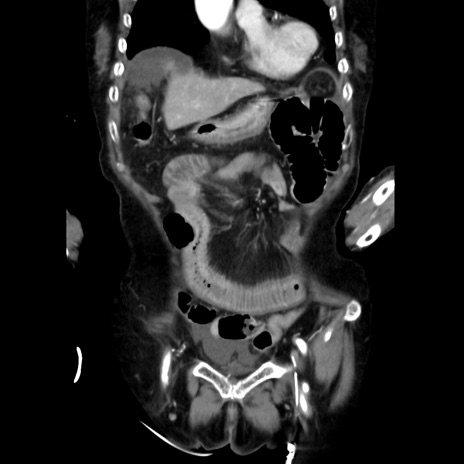

症例40(冠状断像)

【症例】90歳代女性

【主訴】腹痛・嘔吐

【現病歴】 食欲低下、嘔吐があり昨日他院受診。肺炎と診断され入院となる。入院後より腹部全体に圧痛あり。胃管留置され経過みていたが、症状持続するため、

当院転院となる。

【既往歴】胸椎圧迫骨折、胆石症

【身体所見】腹部:中央に激痛あり、圧痛あり、反跳痛不明

【データ】WBC 17100、CRP 18.82

冠状断像